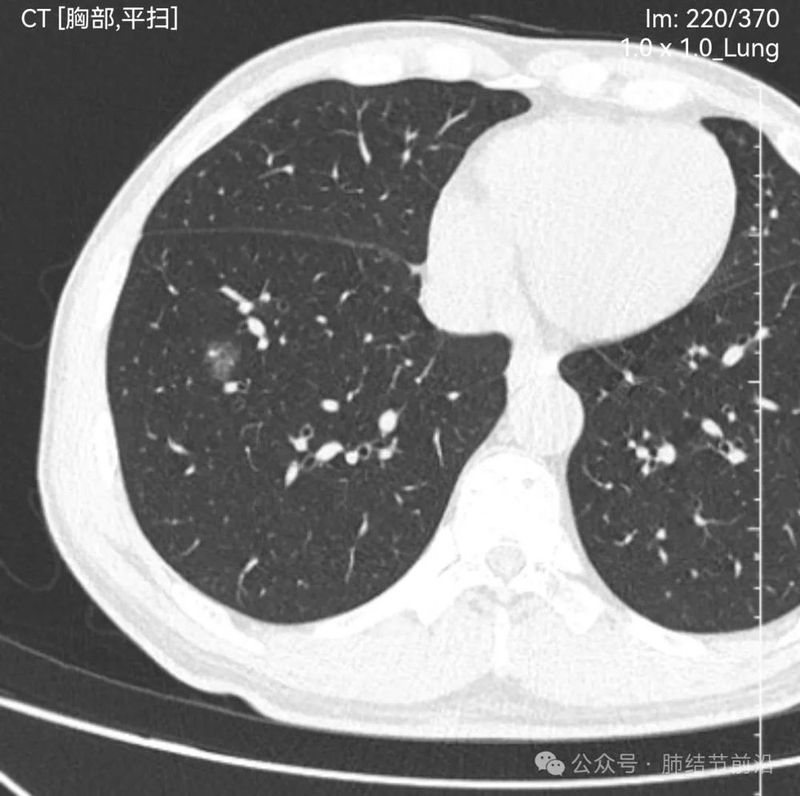

见右下肺纯磨玻璃结节14mm。有“血管穿过”、空泡。磨玻璃边界清楚而不毛糙。形态上是典型的肿瘤性磨玻璃,以微浸润腺癌可能大。